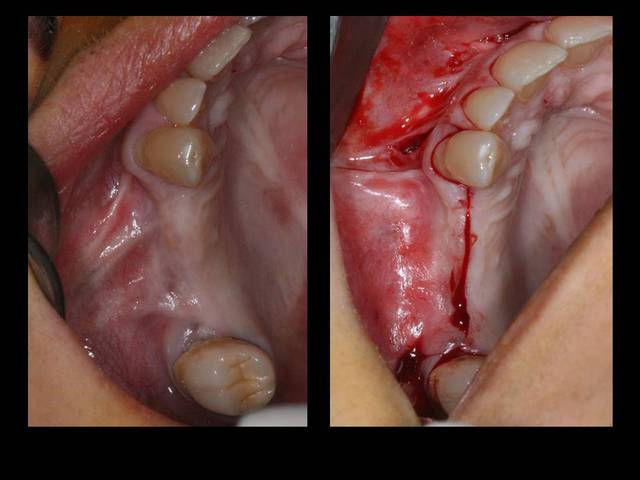

Suite à un post que j'avais mis sur les dégats des gestes iatrogènes dans notre art...

http://www.eugenol.com/sujets/394749-devoir-de-confraternite?page=5

Je poste aujourd'hui la reconstruction.

Les photos donnent la sensation que le manque est palatin mais c'est une illusion liée à la parallaxe.